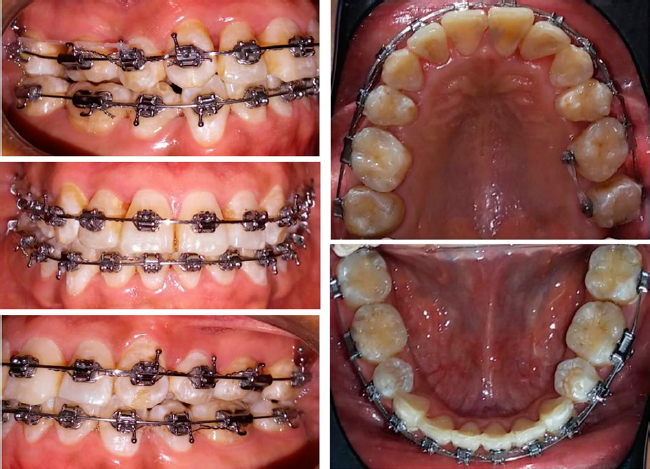

En el análisis facial se determinó una paciente dolicofacial con el tercio inferior aumentado, exposición disminuida de los dientes anteriores superiores al sonreír y perfil recto (Figura 1). A la exploración clínica se identificó dentición permanente con ausencia de los dientes 34 y 44, periodonto reducido estable, mucosa bien irrigada, frenillos bien implantados, líneas medias no concordantes, apiñamiento superior severo e inferior moderado; dientes 13 y 23 en supraoclusión Clase III molar, y mordida cruzada unilateral (Figura 2). Se solicitaron auxiliares diagnósticos incluyendo ortopantomografía y radiografía lateral de cráneo (Figura 3).

Se realizaron extracciones de los dientes 15, 25, 18, 28, 38 y 48. Se colocaron brackets metálicos, aparatología CCO 0.022” X 0.028” y arcos de Nitinol 0.014” en las arcadas superior e inferior para iniciar con la alineación y nivelación. También se ocuparon resortes abiertos de NiTi para incluir el diente 12 (Figura 4). Posteriormente se colocaron arcos 0.016” x 0.022” Nitinol en las arcadas superior e inferior para continuar con la alineación y nivelación. También se indicaron resortes abiertos y ligadura metálica para distalizar los caninos y lograr clases caninas y molares ideales. Se colocaron botones linguales en el primer segundo premolar superior e inferior izquierdo con elásticos para descruzar mordida.